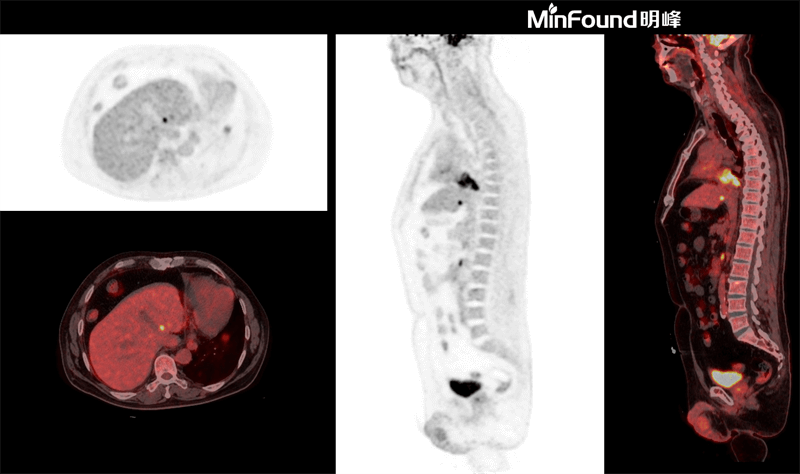

ScintCare PET/CT 730T

ScintCare PET/CT 730T employs a 4th-generation PET detector where lutetium-yttrium oxyorthosilicate (LYSO) crystals are individually coupled to SiPM detectors without the optical conductor (1: 1 coupling and 100% coverage). The digital SiPM detector considerably minimizes photon loss, resulting in improved time resolution (380 ps), system sensitivity (23.5 cps / kBq), and image uniformity, ultimately resulting in high-resolution images under well-curated radiation dose control.

ScintCare PET/CT 730T axial FOV reaches 40.3 cm width, enabling the whole-organ scan just by one-bed position and the whole-body scan by two-bed positions in about 3 minutes time. The ultra-fast data acquisition greatly supports the large patient throughput.

臨床畫(huà)廊